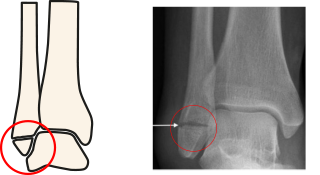

A Weber A fracture is an injury to the fibula, a bone on the outside of the lower leg forming part of the ankle. It is a stable injury commonly occurring when the sole of the foot turns inwards, causing the ligaments on the outside of your ankle to stretch.

The X-rays reviewed by your doctor today confirm that your child has sustained a Weber A fracture.